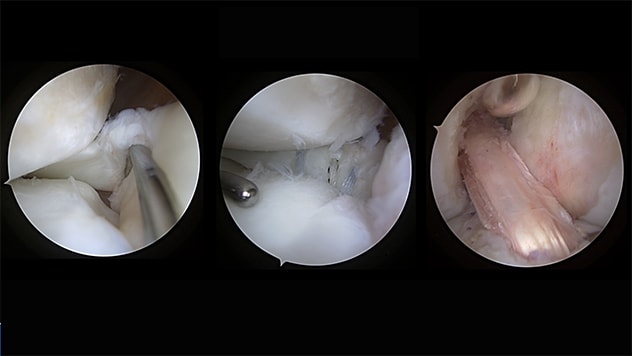

Stage I femoral and tibial bone grafting.

Stage II lateral root tear, lateral root repair and repeat revision back-to-back ACL repair.

A 17-year-old female came to see us after two failed ACL surgeries. Her alignment, tibial slope and cartilage were all normal. Unfortunately, both previous reconstructions were performed with allograft (cadaver) tissue, which has been shown to have significantly higher failure rates in young patients compared with autograft (the patient's own tissue). The patient also had an unrecognized complete disruption of her lateral meniscal root and excessively widened tunnels and sockets.

This case required a two-stage approach: Stage 1 consisted of bone grafting, followed by second-stage repeat revision ACL reconstruction with patellar tendon autograft, lateral meniscal root repair and iliotibial band tenodesis. Two years after the surgery, she resumed all activities and plays collegiate volleyball.